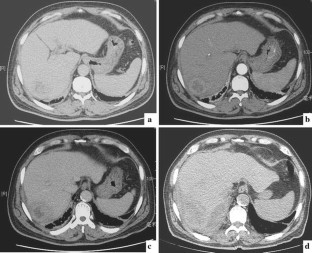

Combined hepatocellular carcinoma and cholangiocarcinoma (cHCC–CC) is a rare form of primary liver cancer (PLC). It is difficult to make a correct preoperative diagnosis of cHCC–CC because of the lack of special features of the disease. We here present a case of a 68-year-old man who presented with fluctuant fever, chills, and sweating and was eventually diagnosed as cHCC–CC after surgery. The tumor was 6.0 cm in diameter with distinct borders and no satellite lesions or lymph nodes were observed during macroscopic examination of the resection specimen. The fever resolved in the postoperative period till the 28th day after surgery, when the patient developed extensive abdominal metastases and died shortly after. More attention should be paid to the patient with PLC showing abnormal features such as FUO, normal range of tumor markers, atypical imaging, and less cirrhosis. Hepatic resection is the treatment of choice although with short-term outcomes.

Fig. 2